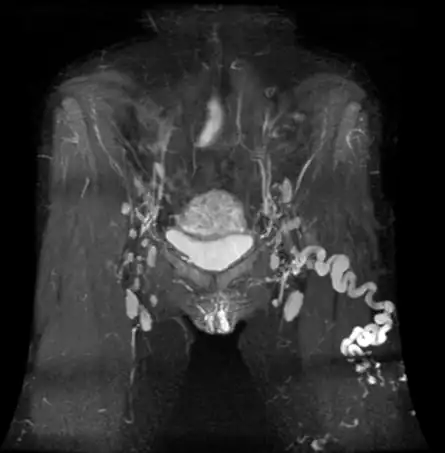

Zmiany Modic to wynik badania rezonans magnetyczny (MRI), który często pojawia się w opisach kręgosłupa osób z przewlekłym bólem pleców. Mogą świadczyć o procesach zapalnych, zwyrodnieniowych i przebudowie trzonów kręgowych, a ich obecność może wiązać się z nasileniem dolegliwości bólowych. W tym wpisie wyjaśniamy, czym są zmiany Modic, jak je rozpoznać, jakie dają objawy i jak wygląda ich leczenie oraz rehabilitacja.